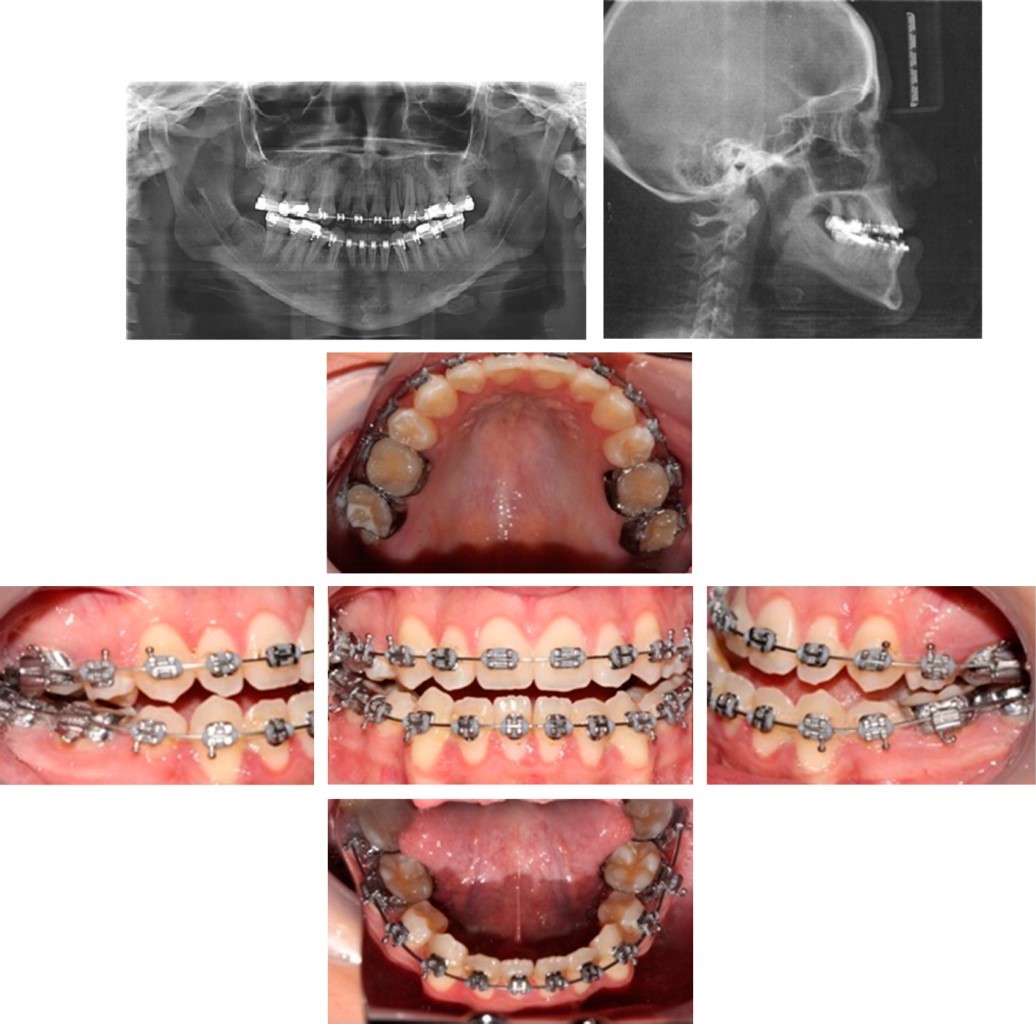

In the pre-surgical orthodontic phase, Roth slot 0.022" × 0.025" brackets were placed, first upper and lower premolars were extracted to relieve the crowding of both arcades, the prescribed sequence of archwires for this technique was followed 0.014", 0.016", 0.016" × 0.022", and 0.017" × 0.025", flexible archwires for alignment and levelling, double key steel archwires (DKL) until the space closure was achieved and reach at 0.019" × 0.025" steel arches necessary for the placement of surgical posts.

Alignment, levelling and dental decompensations were achieved, which at the moment aggravates class III (Figure 3) but the crowding was released and the tripodism necessary for surgical stability was achieved and monitored with several model shots.

Prior to surgery we ensured root parallelism to obtain treatment stability (Figure 4).

In the post-surgery phase, we changed the archwires to TMA 0.017" × 0.025" and intermaxillary elastics, to obtain maximum intercuspidation. In this case, post-surgical tooth movement was limited by the periodontal conditions in the lower arch, as the roots approached the vestibular cortex.